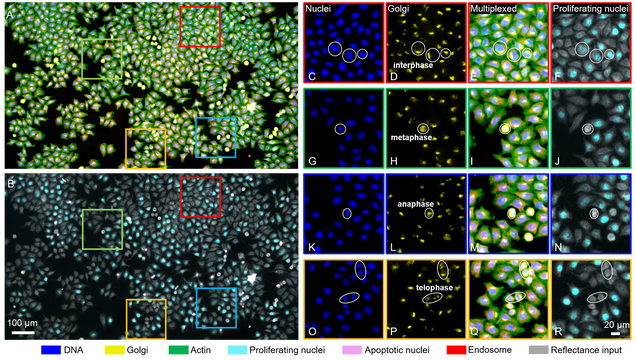

To see what’s going on inside a cell, researchers commonly tag it with fluorescent stains or dyes to identify subcellular structures. But, the cell preparation is tedious, and most methods only allow researchers to view at most three colors at a time, limiting their picture of the cell’s components.

Tian and his colleagues use digital labeling that can apply six virtual fluorescent labels, thereby viewing six aspects of a cell at the same time, such as its DNA, components, and stage in its life cycle.

The group is among the first in cytometry (cell analysis) to use reflectance microscopy: Their custom-built microscope captures back-scattering signals that provide “exquisite sensitivity in detecting nanoscale structural changes,” Tian and co-authors write.

And they are the first to apply deep learning to analyze the reflectance images. “Once you have these beautiful virtual images, to the untrained eye, it’s very difficult to assess whether they’re just beautiful or they’re actually biologically correct,” says Tian. “We showed that this new data-driven imaging cytometry technique is fairly accurate.”

Importantly, some of the parameters that the Tian lab’s method can pick up on with great accuracy include markers for cancer and other diseases that are difficult to detect with current methods.